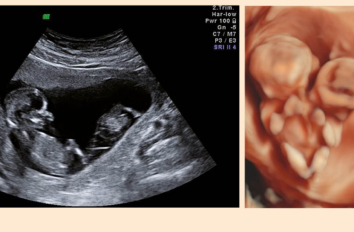

Mehrlingsschwangerschaften

Dr. med.  Ladina Vonzun,  Prof. Dr. med. Nicole Ochsenbein-Kölble

In den letzten 40 Jahren hat sich die Anzahl der Mehrlingsschwangerschaften in der Schweiz praktisch verdoppelt. Während 1979…